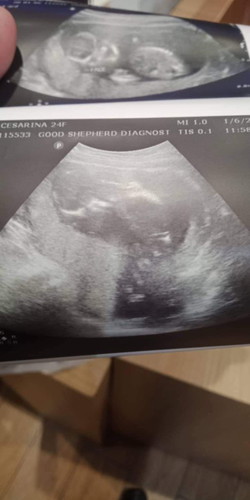

normal lang ba na sa 15weeks andyan tlaga legs ni baby?

normal lang ba na sa 15weeks andyan tlaga legs ni baby? parang palabas na

Iikot pa yan sis .

Ano sabi ng ob?